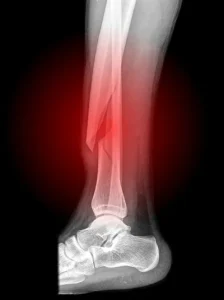

2. Açık Fraktür

Açık fraktür, kemiğin kırılması sonucu cildin delinmesi ve kemiğin dışarıya çıkması durumudur. Bu tür fraktürler genellikle daha ciddi olabilir çünkü enfeksiyon riski daha yüksektir.

Enfeksiyon: Özellikle açık fraktürlerde, enfeksiyon riski artar. Kemiğin dışarıya çıkması, bakterilerin vücuda girmesine yol açabilir.

Kanama: Açık fraktürlerde kanama görülebilir ve bu durum, daha fazla komplikasyona yol açabilir.